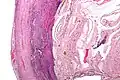

Pathology

Even for clinically certain appendicitis, routine histopathology examination of appendectomy specimens is of value for identifying unsuspected pathologies requiring further postoperative management.[58] Notably, appendix cancer is found incidentally in about 1% of appendectomy specimens.[59]

Pathology diagnosis of appendicitis can be made by detecting a neutrophilic infiltrate of the muscularis propria.

Periappendicitis, inflammation of tissues around the appendix, is often found in conjunction with other abdominal pathology.[60]

-

Micrograph of appendicitis and periappendicitis. H&E stain. -

Micrograph of appendicitis showing neutrophils in the muscularis propria. H&E stain. -

Acute suppurative appendicitis with perforation (at right). H&E stain.